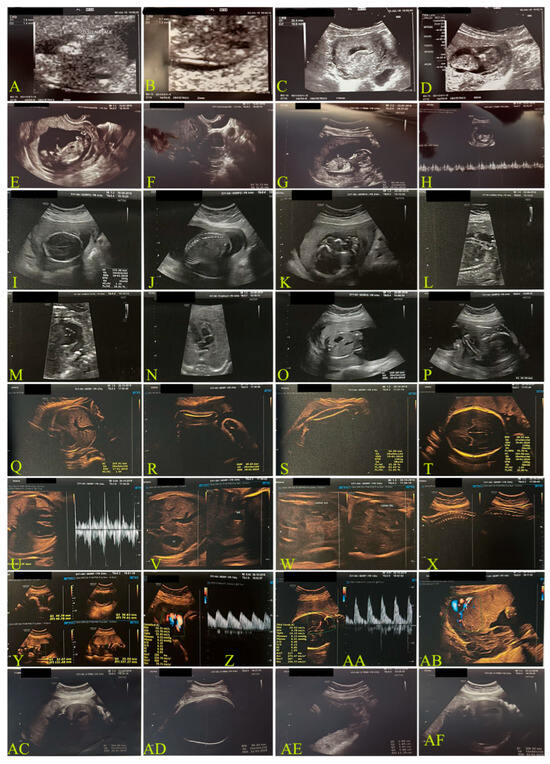

2.1.2. Second Case: COVID-19 Pandemic, 2022–2023, Omicron Variant, Same Mother as the Above-Mentioned Case (Figure 2)

| Weeks of gestation and Ultrasound data | 20 + 2 days | 21 + 1 days | 20 + 4 days |

| Biparietal diameter (BPD) | 47 mm | 52 mm | 46.4 mm |

| Occipital-frontal diameter (OFD) | 61 mm | 67 mm | - |

| Head circumference (HC) | - | 190 mm | 178 mm |

| Thermal index for bone (TIB) | - | 31 mm | - |

| Fetal corpus callosum (CC) | 172 mm | 190 mm | - |

| Cerebellum transverse diameter | 20.5 mm | 21.5 mm | - |

| Lateral trigon diameter (Lateral Ventriculum) | 6.8 mm | 6 mm | - |

| Abdominal circumference (AC) | 150 mm | 166 mm | 145 mm |

| Femur length (FL) | 32 mm | 36 mm | 32.3 |

| Occiput lateral (head down, facing your side) (OL) | - | 33 mm | - |

| Heart rate | 151 bpm | 140 bpm | 140 bpm |

| Estimated weight | 330 g | 430 g | 320 g |

| Weeks of gestation and US data | 29 days | 28 + 1 days | 31 days |

| Biparietal diameter (BPD) | 69 mm | 72 mm | 79 mm |

| CC | 258 mm | 253 mm | 280 mm |

| Cerebellum transverse diameter | 30 mm | 21.5 mm | - |

| AC | 246 mm | 250 mm | 273 mm |

| LF | 49 mm | 58 mm | 56 mm |

| Estimated weight | 1230 g | 1451 g | 1600 g |

| Week | 15 + 2 Days | 21 + 1 Day | 24 + 5 Days | 28 + 1 Day |

|---|---|---|---|---|

| MAF | YES | YES | YES | YES |

| Heart rate | 163 bpm | 140 bpm | 160 bpm | 168 bpm |

| Biparietal Diameter (DPB) | 35 mm (68° pc) | 52 mm | 63 mm | 72 mm |

| Head circumference (HC) | 117 mm (31° pc) | 190 mm | 230 mm | 253 mm |

| Femur length (FL) | 19 mm (45° pc) | 36 mm | 44 mm | 58 mm |

| Abdominal circumference (AC) | - | 166 mm | 206 mm | 250 mm |

| Estimated fetal weight | 218 g | 430 g | 750 g | 1451 g |

| Percentile of weight | 97.5th | 67.3th | 52.5th | 97.5th |